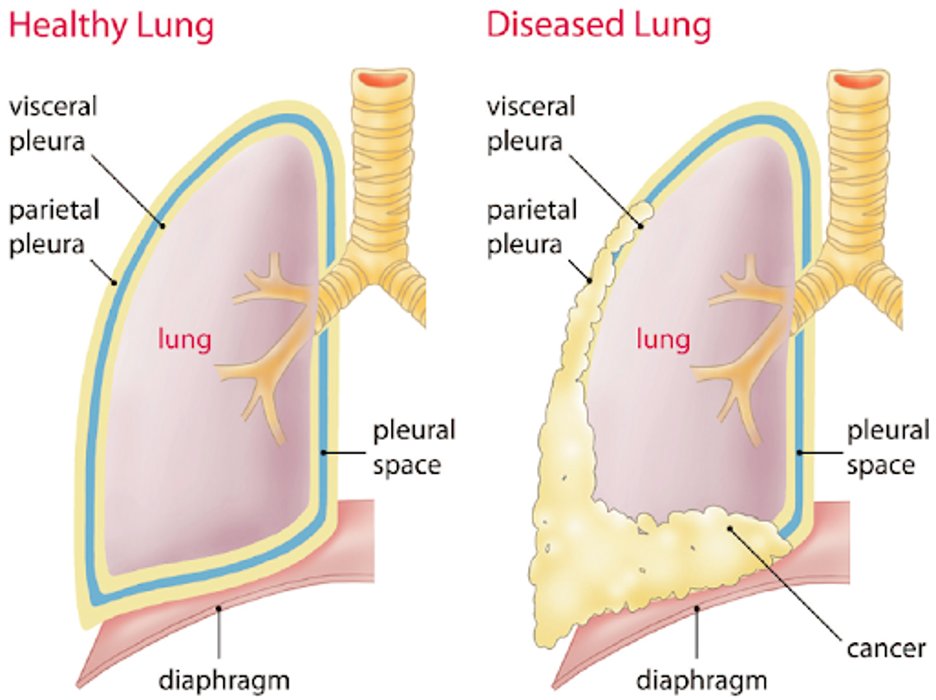

2/Let’s first start with some definitions. The term “non-expandable lung” is an umbrella term that is used to describe when the lung is unable to expand to the chest wall in order to achieve visceral and parietal pleura apposition. @AvrahamCooperMD @michellebr00ks @mdlizs

3/There are two pleural diseases that result in the “non-expandable lung”:

4/Lung entrapment is when the lung cannot fully expand due to an active disease that restricts the expansion of the lung and/or visceral pleura. This is typically associated with an exudative effusion. @tony_breu @KevinSwiatek

5/ Trapped lung is when the lung cannot expand due to a remote inflammatory condition that leaves a collagenous or fibrinous peel on the viscera pleura that prevents lung expansion. The pleural fluid can be transudative or exudative. @scall1200 @cderekleiner @rva_IntMedPD

6/Let’s dive into lung entrapment. The most common cause of lung entrapment is due to pleural malignancy with an estimated 30% of malignant effusions leading to lung entrapment. However, pleural infections or inflammation can also lead to lung entrapment.